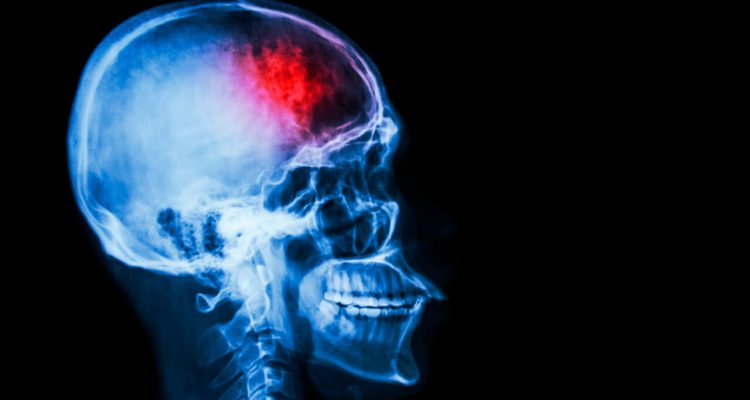

Професор Дональд Вівер з Університету Торонто пропонує альтернативний підхід: хвороба Альцгеймера може бути аутоімунним розладом. На думку дослідника, бета-амілоїд — це нормальний білок, залучений до імунної відповіді мозку. Проте через схожість мембран клітин мозку та бактерій імунна система іноді атакує власні нейрони. Це запускає хронічний процес руйнування клітин мозку, що з часом призводить до деменції.

Цей підхід дозволяє переглянути способи лікування. Традиційні методи, спрямовані на знищення бета-амілоїдних бляшок, можуть бути помилковими. Натомість майбутні терапії повинні враховувати механізми імунної регуляції мозку, щоб зменшити аутоімунну реакцію.